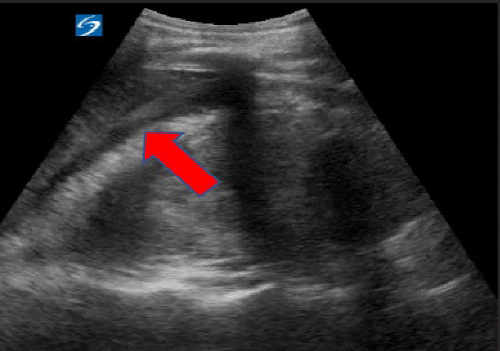

On HD 6, the patient's clinical status deteriorated with worsening shortness of breath, hypoxia, and right flank pain. A chest X-ray (CXR) revealed a new finding of diffuse opacification of the right chest secondary to a large right pleural effusion. A subsequent CT scan confirmed the presence of significant right water density pleural effusion and extravasation of contrast-enhanced urine from the mid-pole calyx into the surrounding right perirenal collection (Figure 3).

Figure 3. CT Scan on Hospital Day 6. Published with Permission

A) Contrast-enhanced CT scan showing a large pleural effusion in the right chest cavity

B) Delayed CT imaging, demonstrating extravasation of urine from the mid-pole calyx of the right kidney.